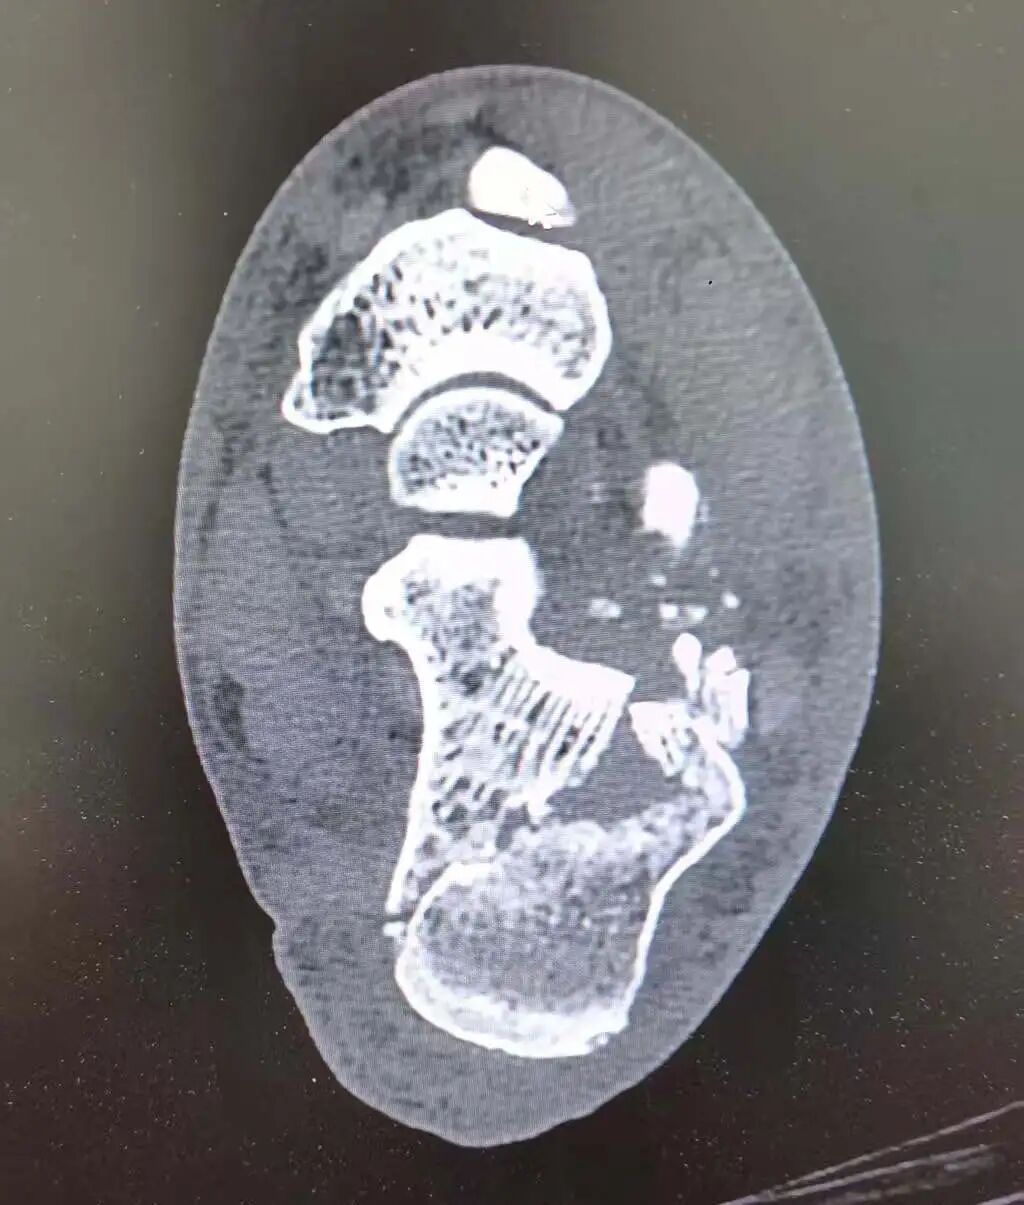

术前